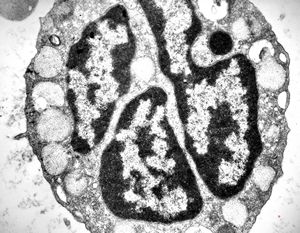

bone marrow - crystalloid inclusions Charcot-Leyden crystals formation

bone marrow - crystalloid inclusions Charcot-Leyden crystals formation v.s.